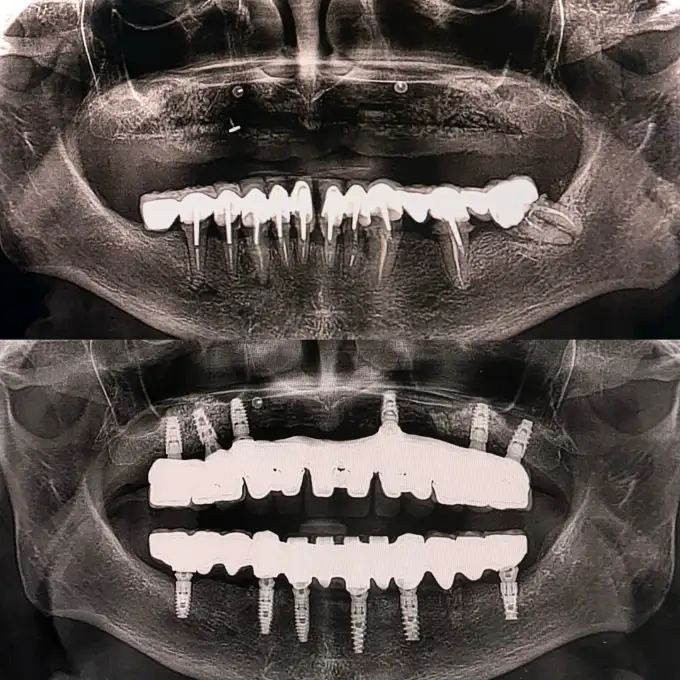

Your treatment begins with a complete evaluation using 3D scans and digital imaging. This allows our specialists to locate bone loss, measure bone density, and plan a graft suited to your needs. We perform grafting after extractions, before implant placement, and for loose teeth that need added support.